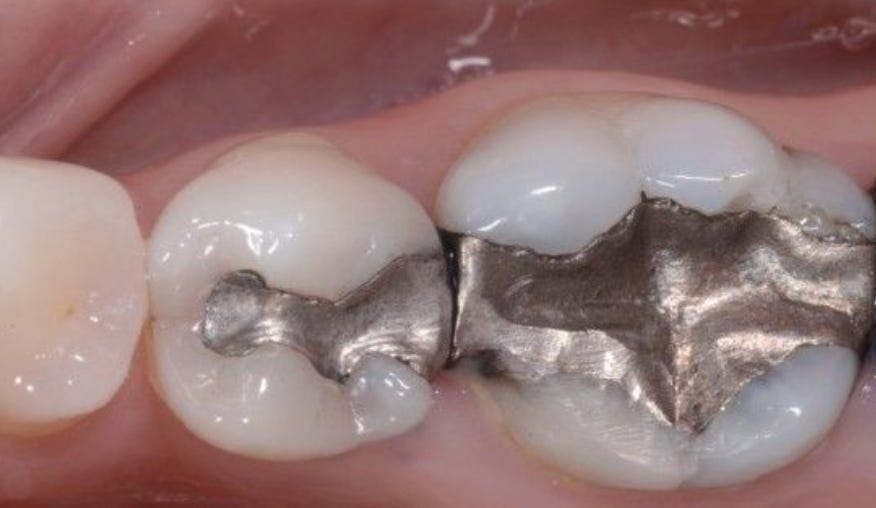

Amalgam Fillings: A Chronic Source of Inflammation

Dental amalgam fillings—commonly referred to as “silver fillings”—are composed of roughly 50 percent elemental mercury, combined with silver, tin, and copper. Mercury is a well-documented neurotoxin with no known safe level of exposure, and amalgam fillings continuously release mercury vapor, especially during chewing, grinding, or exposure to heat. This vapor is readily absorbed through the lungs and oral tissues and can accumulate in the brain, kidneys, and nervous system. Dr. Levy and others argue that this represents a chronic, low-grade toxic burden that can impair mitochondrial function, disrupt immune regulation, and worsen oxidative stress over time. While amalgams have been normalized for decades, their continued use persists more out of institutional inertia than biological safety, particularly when safer alternatives exist.3 Finding a biological dentist to remove fillings is an option to consider.